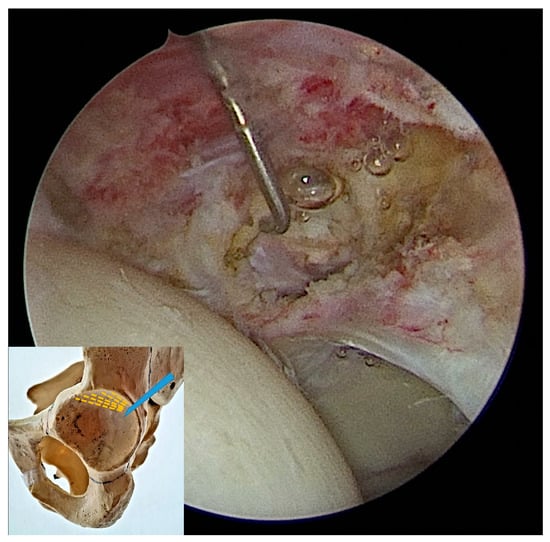

2.2. Surgical Procedure